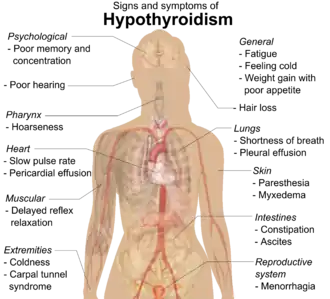

People with hypothyroidism often have no or only mild symptoms. Numerous symptoms and signs are associated with hypothyroidism and can be related to the underlying cause, or a direct effect of not having enough thyroid hormones.[16][17] Many symptoms of hypothyroidism are otherwise common and do not necessarily indicate thyroid problem.[3] Hashimoto's thyroiditis may present with the mass effect of a goiter (enlarged thyroid gland).[16] In middle-aged women, the symptoms may be mistaken for those of menopause.[12]

| Symptoms[16] | Signs[16] |

|---|---|

| Fatigue | Dry, coarse skin |

| Feeling cold | Cool extremities |

| Poor memory and concentration | Myxedema (mucopolysaccharide deposits in the skin) |

| Constipation, dyspepsia[18] | Hair loss, Sign of Hertoghe |

| Weight gain with poor appetite | Slow pulse rate |

| Shortness of breath | Swelling of the limbs |

| Hoarse voice | Delayed relaxation of tendon reflexes |

| In females, heavy menstrual periods (and later light periods) | Carpal tunnel syndrome |

| Abnormal sensation | Pleural effusion, ascites, pericardial effusion |

| Poor hearing | |

| Muscle weakness |

Delayed relaxation after testing the ankle jerk reflex is a characteristic sign of hypothyroidism and is associated with the severity of the hormone deficit.[8]